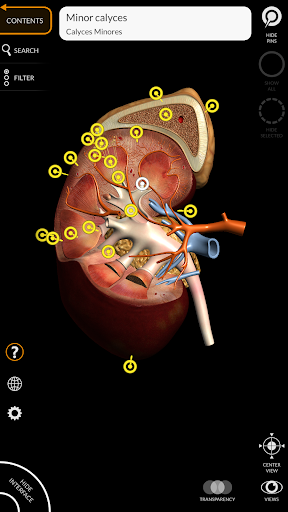

يتيح لك "Anatomy 3D Atlas" دراسة التشريح البشري بطريقة سهلة وتفاعلية.

من خلال واجهة بسيطة وبديهية، من الممكن ملاحظة كل بنية تشريحية من أي زاوية.

تتميز النماذج التشريحية ثلاثية الأبعاد بتفاصيل خاصة ودقة تصل إلى 4K.

نماذج تشريحية ثلاثية الأبعاد

• الجهاز البولي التناسلي (للذكور والإناث)

• تدوير وتكبير كل نموذج في مساحة ثلاثية الأبعاد

• خيار إخفاء أو عزل نموذج واحد أو نماذج متعددة مختارة

• وظيفة الشفافية

• من خلال تحديد نموذج أو دبوس، يظهر المصطلح التشريحي ذي الصلة